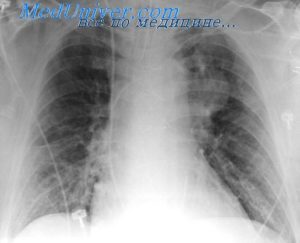

Клинически повторное заболевание, как правило, проявляется значительно сильнее, чем первичный случай. Однако на начальных этапах его трудно распознать, поскольку пациент может считать, что вновь появившиеся симптомы являются следствием ранее перенесенной болезни. Рентгенологическое обследование легких играет ключевую роль в определении характера протекания заболевания.

- Рентгенологическое исследование демонстрирует увеличение пораженной области или изменение характера заболевания на очаговое, что подразумевает наличие множественных поражений.

Установить более точный диагноз с определением степени поражения легкого (также, как распознать бронхит у ребенка и любое другое бронхолегочное заболевание) можно с помощью рентгенографии.

В медицинских источниках можно встретить различные определения повторной пневмонии. В педиатрической практике это заболевание характеризуется как два или более случая в течение одного календарного года, либо более трех эпизодов за неограниченный период времени. При этом рецидив подтверждается рентгенографическими данными, которые показывают освобождение легочной ткани при наличии инфильтрации.